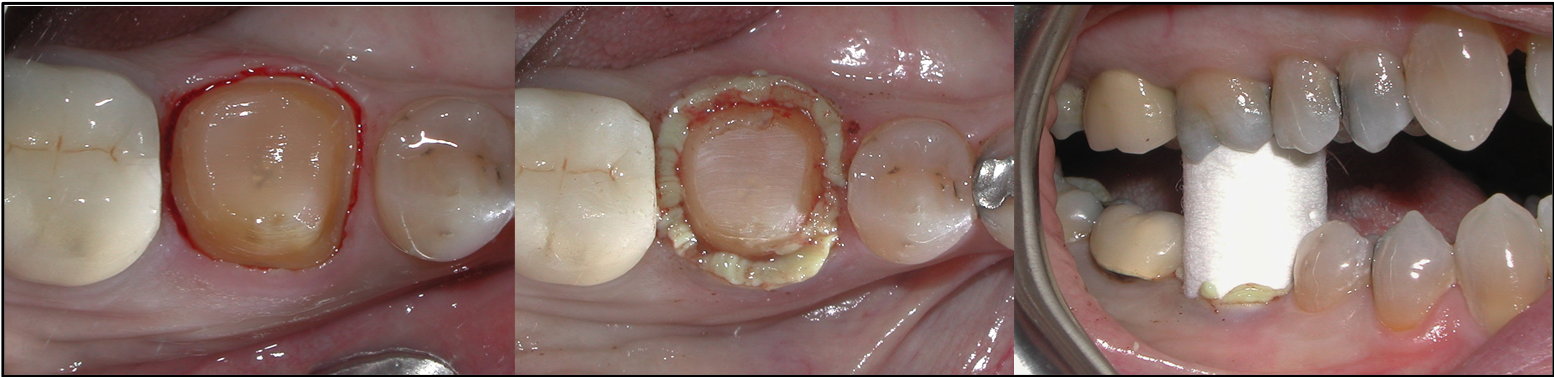

Tooth preparation should be performed as dictated by the type and substrate of the final restoration. Various types of restorations and substrates require different preparation methods. For example, lithium disilicate, porcelain-fused-to-metal (PFM), and porcelain-fused-to-zirconia (PFZ) anterior crown preparations require 1.5 to 2.0 mm incisally, 1.5 mm facially and lingually, and 1.0 mm at the cervical third facially and lingually. Full zirconia crowns in the posterior require 1.0 mm at the cusp tips, 1.5 mm occlusally, 1.0 mm buccally and lingually, and .75 mm at the marginal areas (gingival third of the tooth). Lithium disilicate, PFM, and PFZ posterior crowns require 1.5 to 2.0 mm occlusally, 1.5 mm buccally and lingually, and 1.0 mm at the gingival third or at the margin area (Figure 2).

Fig 2. Different restorations and substrates require different preparation measurements.

Figure 2